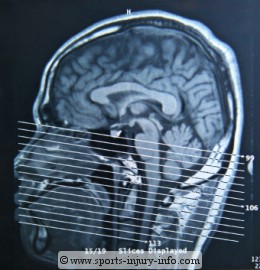

Head CT Scan

Aside from rest, there is little you can for concussions. You should stop activity until symptoms are no longer present. This includes sports, and may even include school attendence. Concussion experts recommend both physical and mental rest. Activities like schoolwork and reading can slow the recovery from a concussion. Injuries with symptoms lasting for more than a few hours should be evaluated in the hospital, and often warrant and MRI or CT scan to rule out any structural damage.